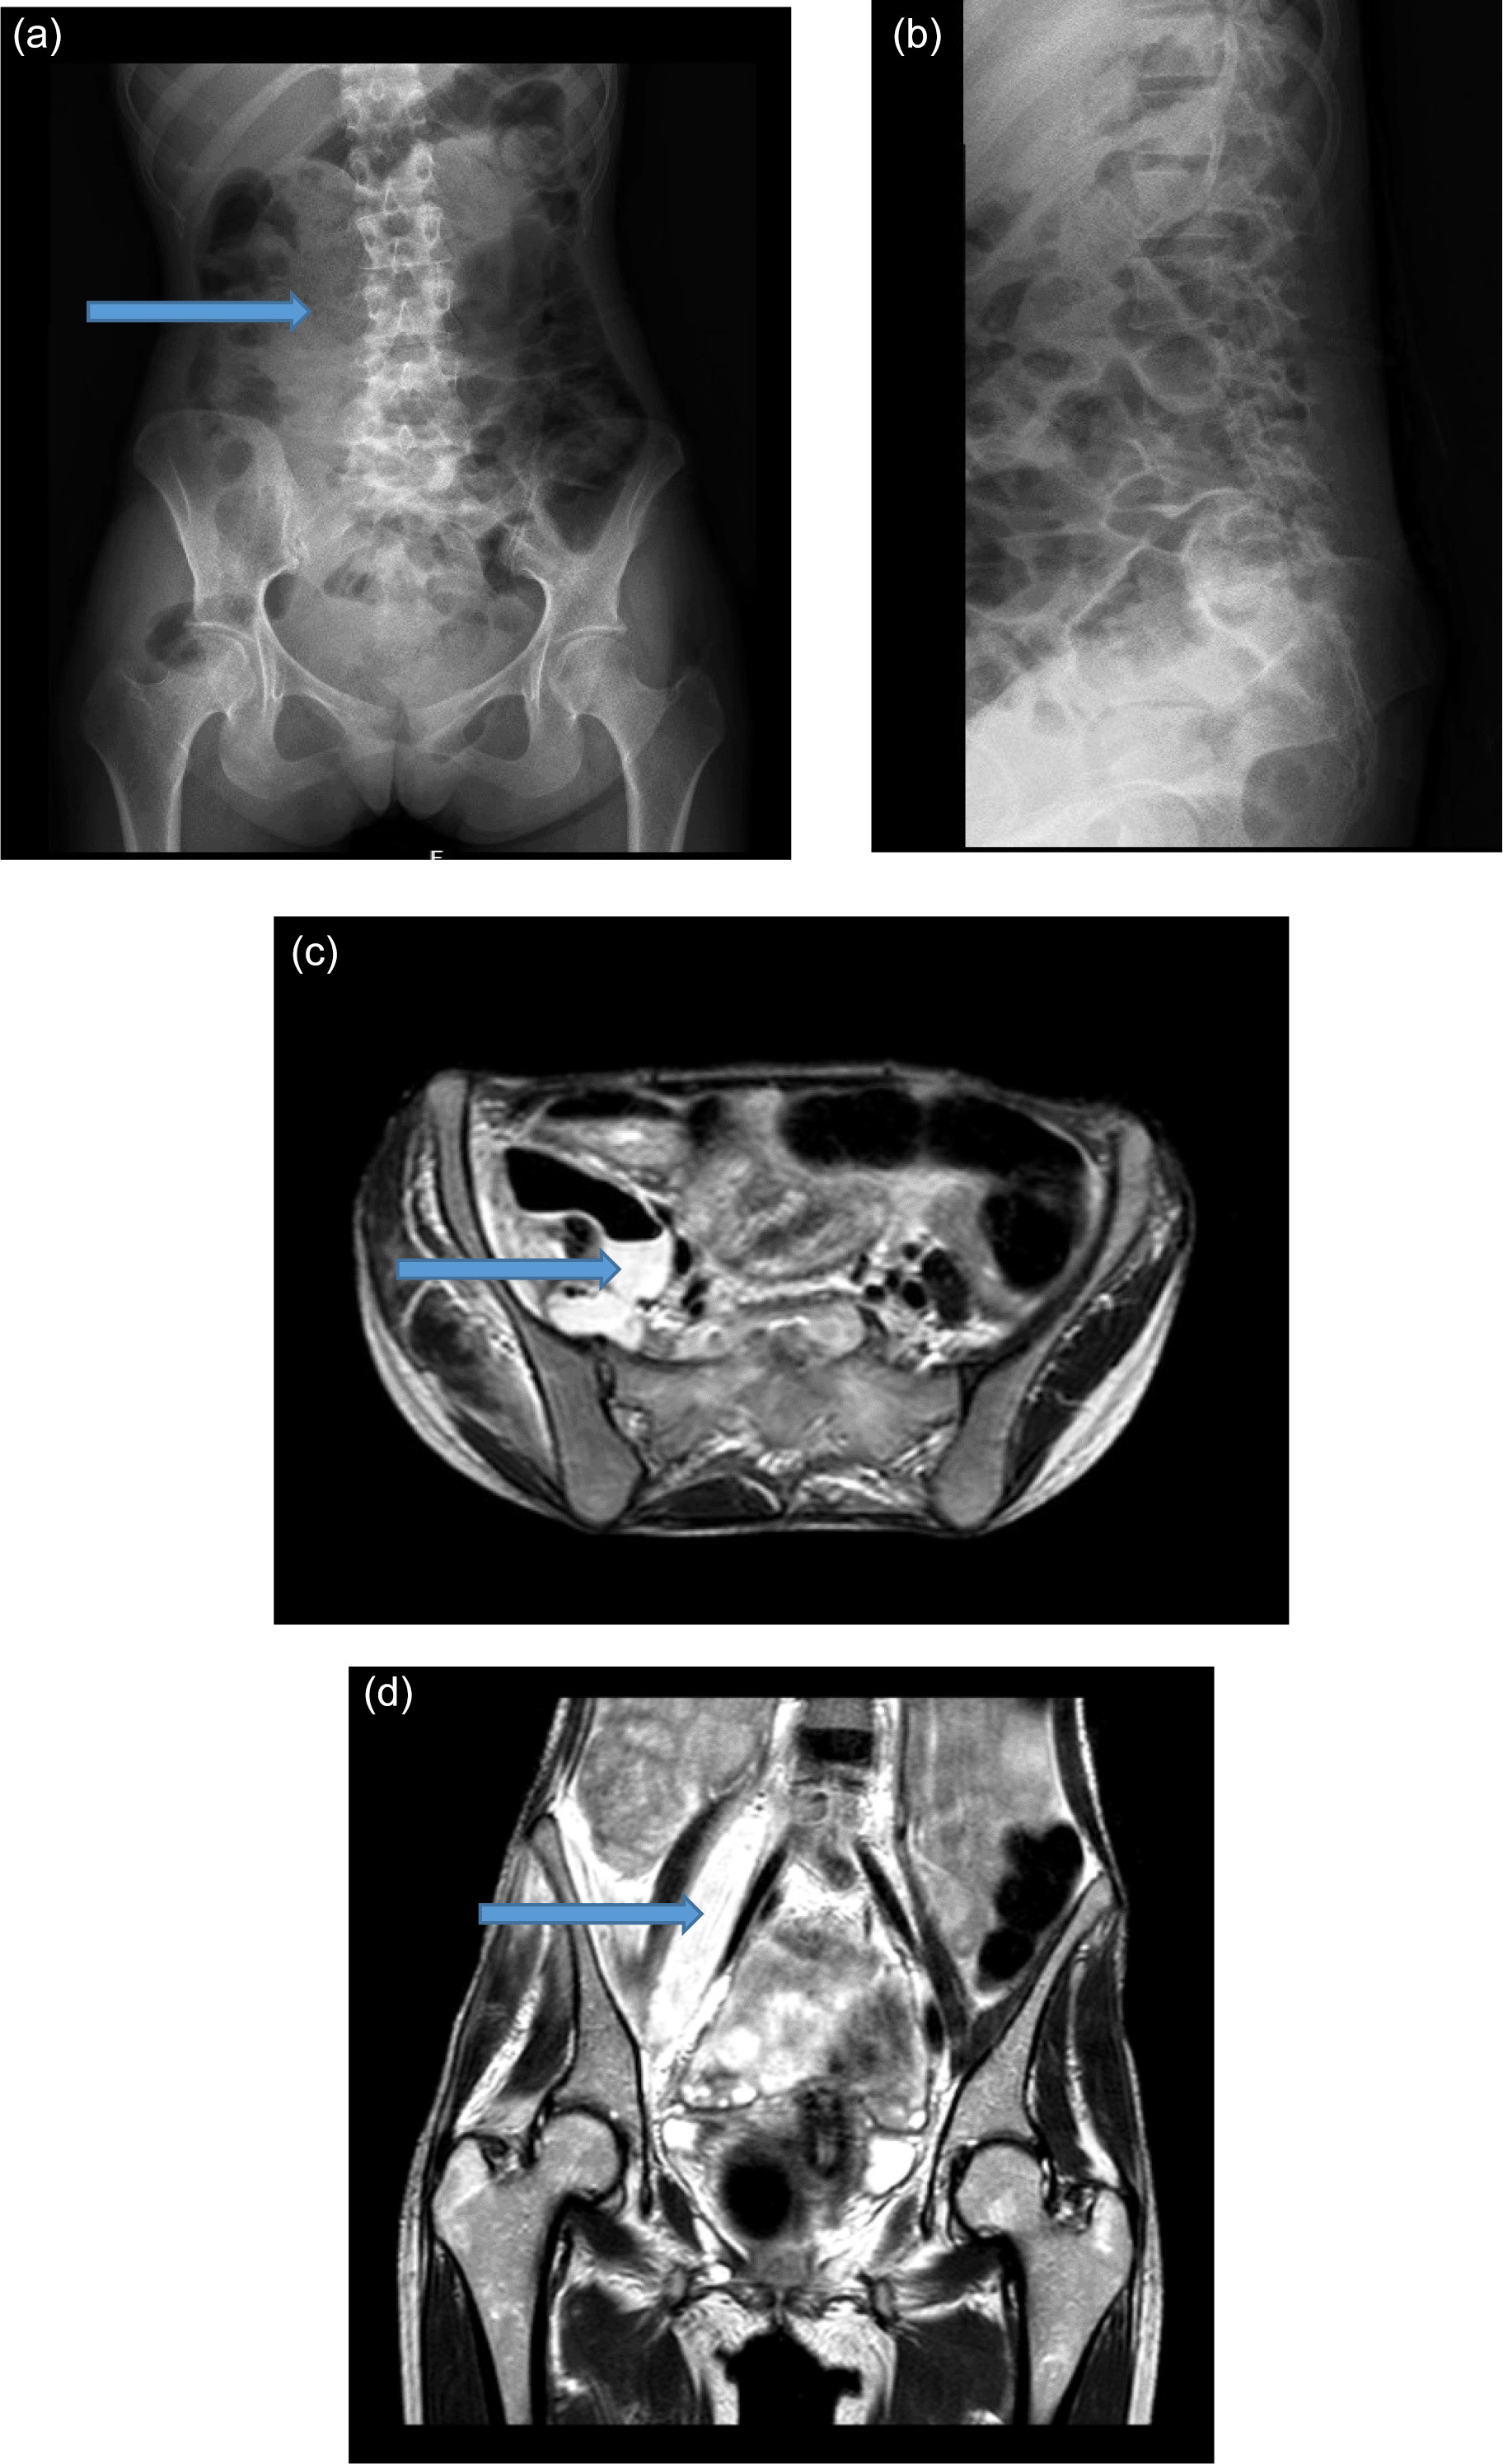

A radiograph revealed mild lumbar scoliosis to the left side and bulky psoas muscle in the right side (Figure 1a and b).

MRI spine revealed features suggestive of spondylodiscitis of L5-S1, spondylitis of L4 with abscesses adjacent to L4, L5, S1, S2 and S3 vertebra in the right side. There was also air-fluid level in the abscess (Figure 1c and d).